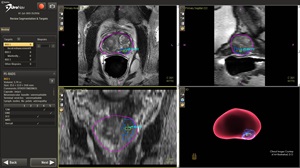

- Build the MRI "Map": We mark the prostate and any PI-RADS 3–5 lesion(s) on your MRI files to create a 3D model.

- Align MRI to Live Ultrasound (Registration): The fusion software aligns your MRI model with real-time ultrasound using elastic registration (molding the MRI to the ultrasound) for precise landmark matching.

- Targeting—See It, Aim It, Sample It: Each MRI target appears inside the ultrasound view. A tracked needle path ensures accurate sampling of multiple targeted cores per lesion.

- Saved "Map" for Continuity: Every core is logged on the 3D map with coordinates for Active Surveillance follow-up or future treatment planning.